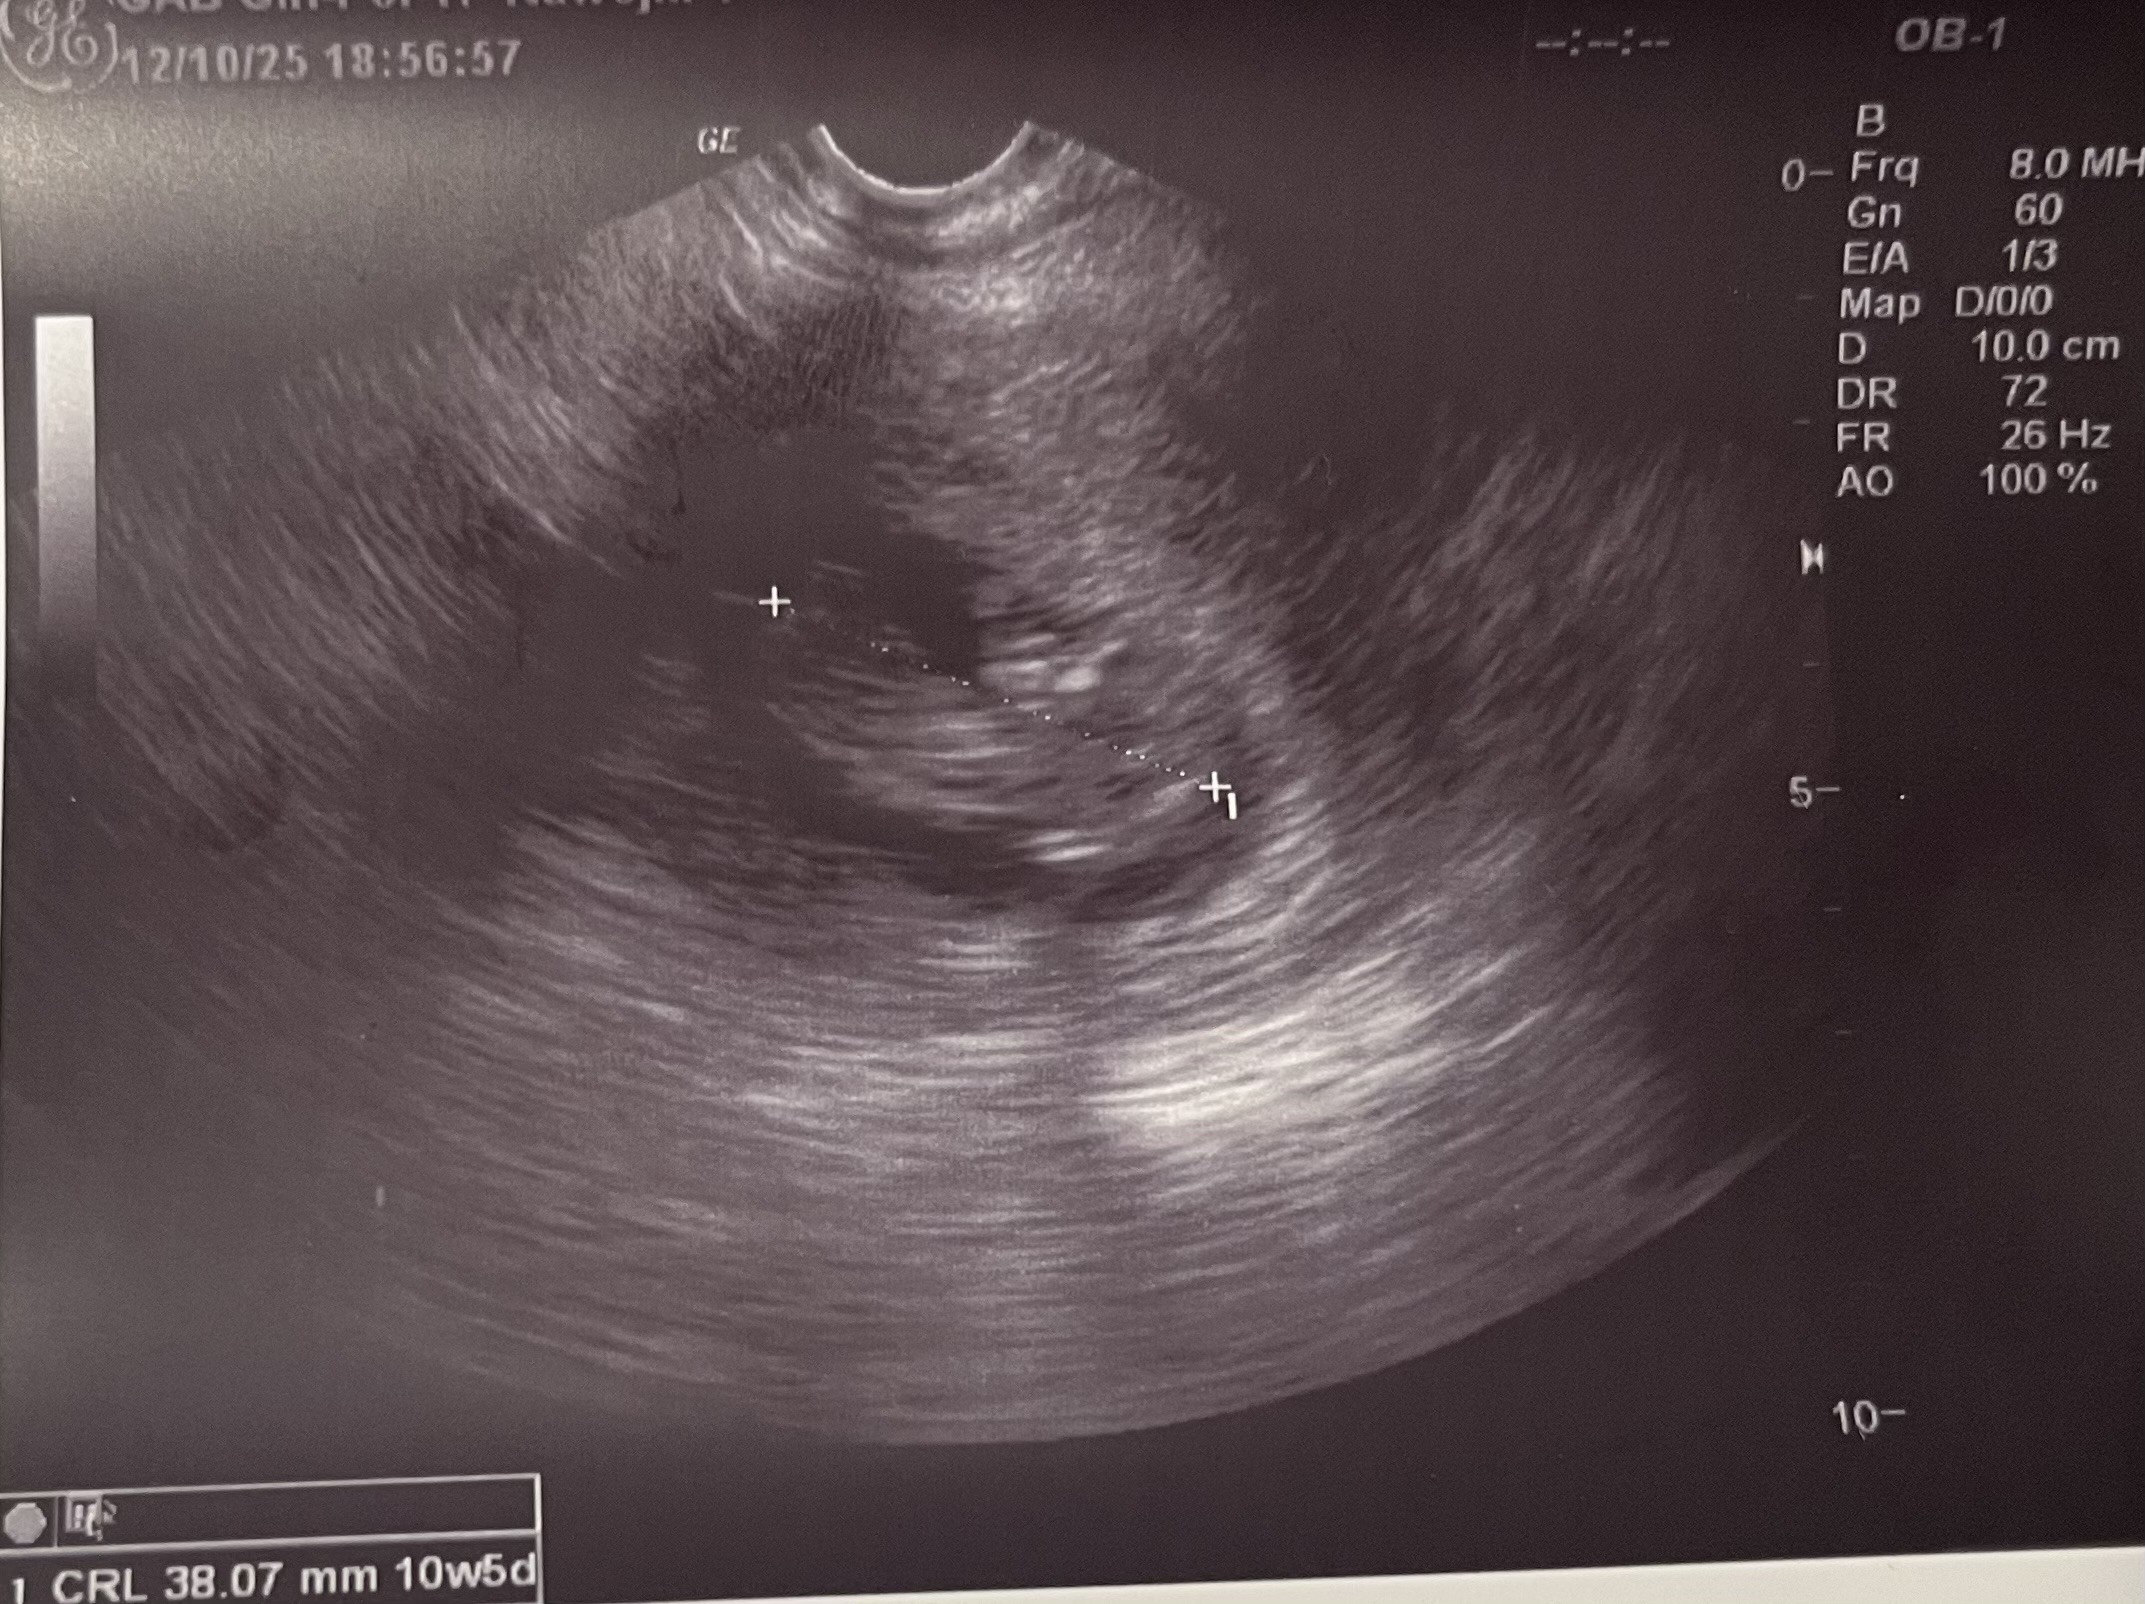

Zdjęcie okruszka z dziś, ma 3,8 cm

. Mam nadzieję, że chociaż u niego wszystko dobrze i zdrowo się rozwija.